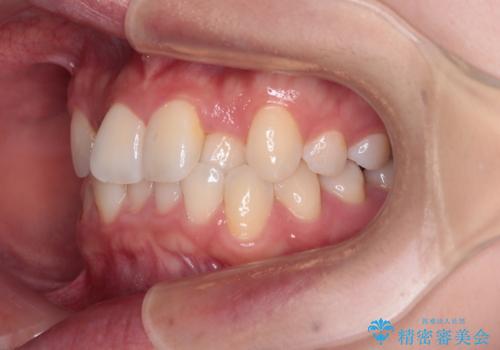

前歯のクロスバイト 裏側に隠れた歯をワイヤー装置で短期間治療

- 上顎前歯のクロスバイトを気にして来院された患者様です。

想定通り、1年強で綺麗に仕上げることができました。